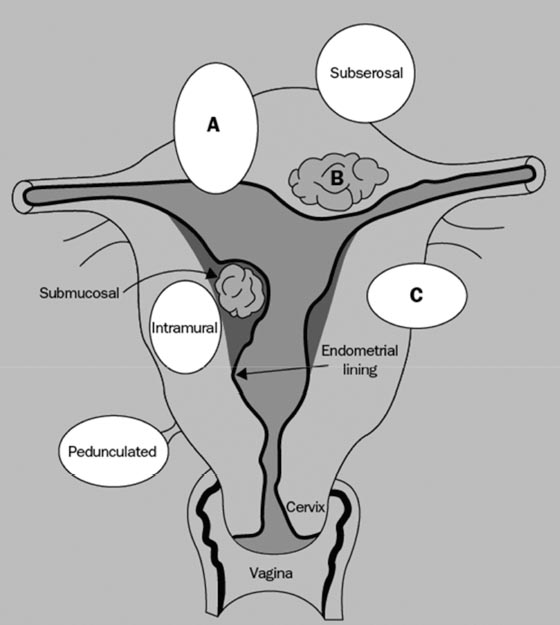

leiomyoma fibroid uterine uterus types fibroids ppt location primary three there leiomyomas powerpoint presentation multiple classified primarily according most slideserve

pathogenesis fig leiomyomas leiomyoma classification reproductive concepts procedural uterine surgical impact medical current management health figo

uterine fibroids bleeding leiomyoma leiomyosarcoma fibroid abnormal endometrial intramural submucosal subserosal pedunculated malignancy cervical hyperplasia sarcomas lecturio

leiomyomas uterine clinical review location radiology key

Uterine leiomyomas, current concepts: pathogenesis, impact on. Uterine leiomyoma at 10x magnification. Pathogenesis fig leiomyomas leiomyoma classification reproductive concepts procedural uterine surgical impact medical current management health figo